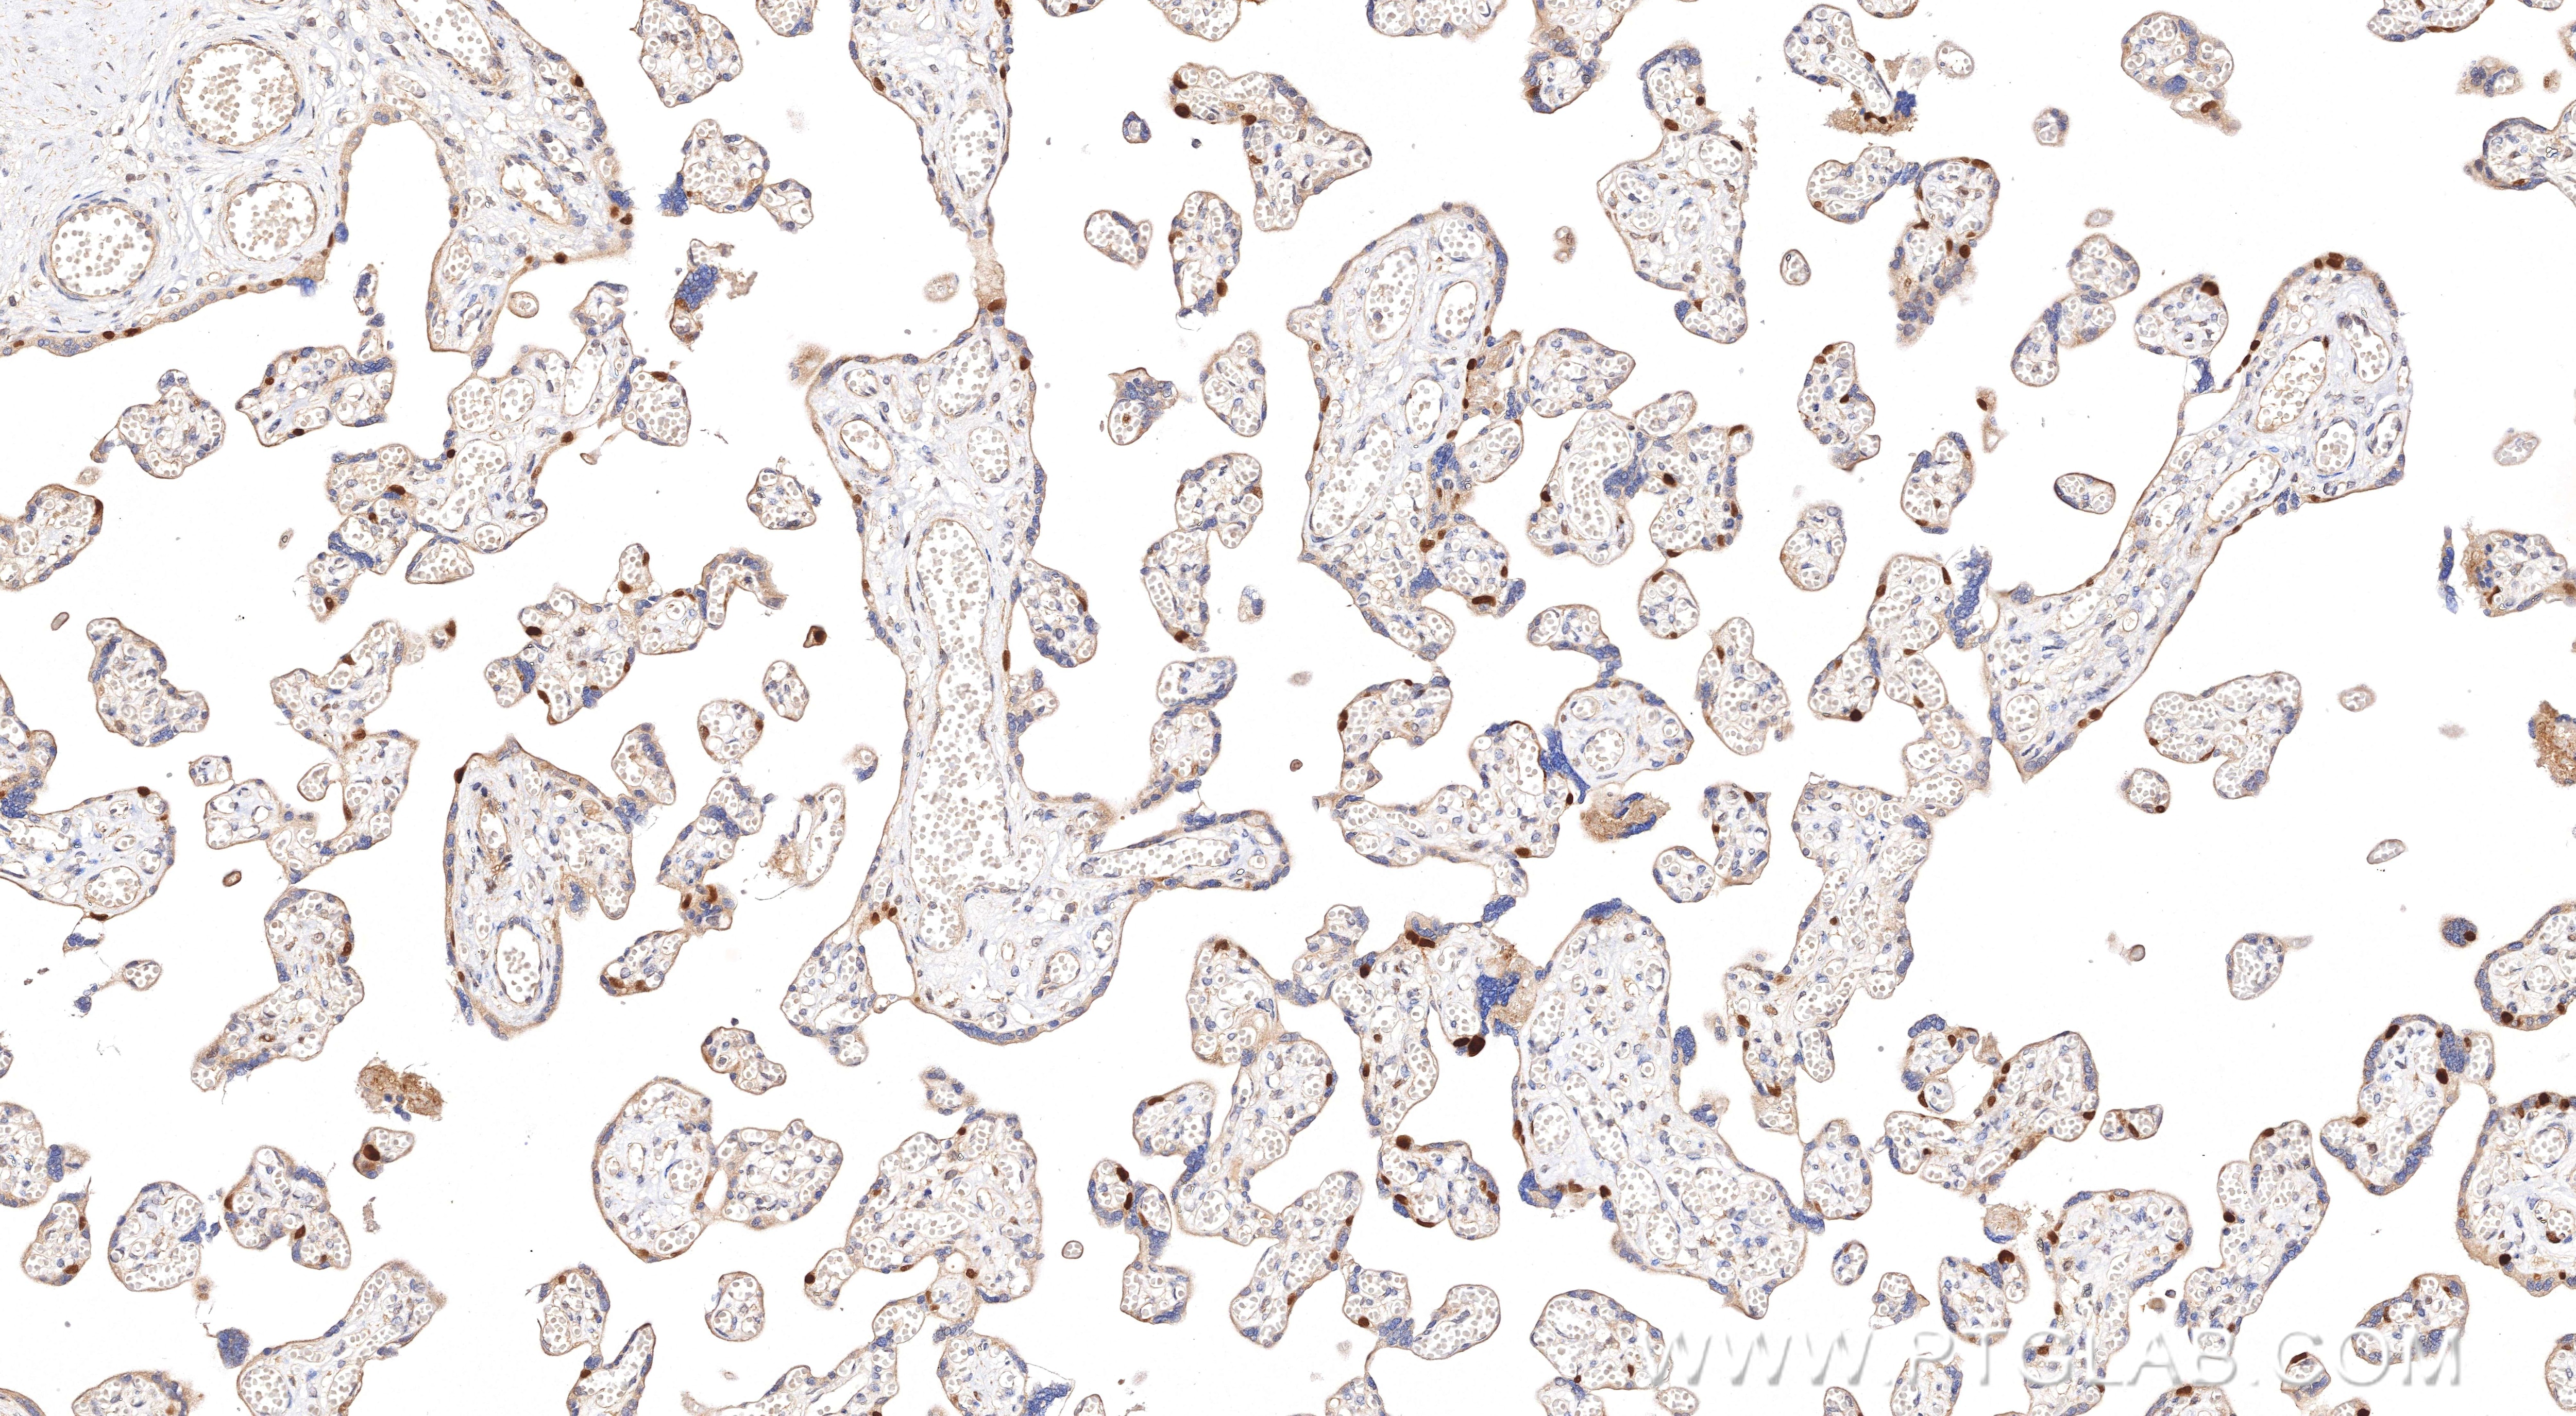

| Positive IHC detected in | human placenta tissue Note: suggested antigen retrieval with TE buffer pH 9.0; (*) Alternatively, antigen retrieval may be performed with citrate buffer pH 6.0 |

| Immunohistochemistry (IHC) | IHC : 1:500-1:2000 |